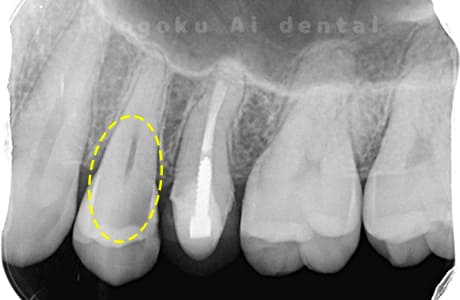

Case05

- 原因

- 15部重度カリエス

-

- 治療内容

- 断髄治療

- 治療費用

- 66,000円

歯がしみるとのことで来院された患者様です。虫歯が神経まで及んでいましたが、神経を一部分カットする断髄治療を行いました。経過も良好です。

<リスク・副作用>

術後は痛み、腫れ、痺れなどの副作用が生じる場合があります。症状が再発する可能性があります。その場合は抜髄する必要があります。